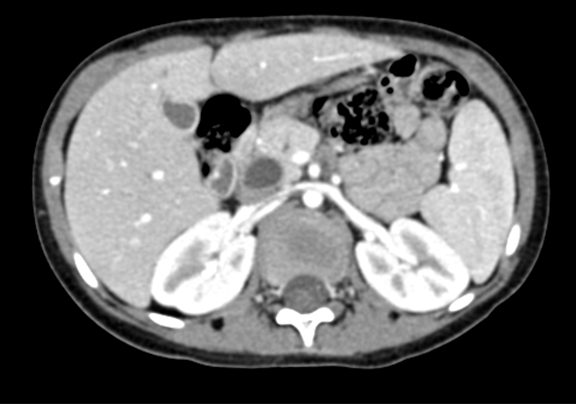

上腹部CT 动态增强:1. 肝内部分胆管-肝门部胆管-胆总管扩张,符合先天性胆管扩张症2. 胆总管下段腔内结节状略高密度影,伪影?结石?3. 胆囊壁略厚,提示胆囊炎可能。

术前CT检查:

动脉期

静脉期

平衡期